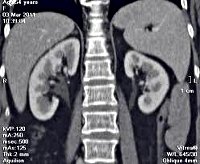

Компьютерная томография (КТ) почек. Это исследование почек для получения изображения слой за слоем с помощью рентгеновского излучения. КТ почек используется для диагностики травматических повреждений, опухолей, патологий, гидронефроза, мочекаменной болезни, абсцессов и кист. КТ почек используется для исследования забрюшинного пространства и надпочечников, для определения места удаления материала во время биопсии и для мониторинга почек у пациентов в послеоперационном периоде. Для более осмысленного обследования можно отработать введение контрастного вещества пациенту. КТ почек противопоказан при тяжелой почечной недостаточности, беременности, лактации, декомпенсированном сахарном диабете и общей тяжести заболевания.

КТ почек относится к современным методам лучевых исследований, которые позволяют получать изображения отдельных слоев (томограмм) почек с толщиной среза 1-10 КТ почек гораздо более информативен, чем обзорная урография, и дает представление о детальном состоянии органов, наличии изменений, их локализации и распространенности. Цвет полученного изображения отражает количество поглощенной энергии рентгеновского излучения и плотность тканей, выявляя наличие объемной массы и других повреждений. Для лучшей дифференцировки таза, паренхимы и мочеточника рентгеноконтрастные агенты используются при КТ почек. При необходимости компьютерная томография почек может быть дополнена другими исследованиями мочевыводящих путей - УЗИ почек, УЗИ почечных сосудов, МРТ, биопсия почки, ангиография и венография почек.

Оценка результатов

Топография почек оценивается с помощью КТ относительно соседних образований. Размер и форма почек определяется пересечением полюсов и их контуров. Неизмененная паренхима почек имеет немного более высокую плотность, чем печень, но во много раз меньше плотности костной ткани. На нативных томограммах пробирки для сбора показаны темным цветом; С введением контраста их плотность увеличивается, а тень становится ярче. Плотность образования массы, определяемая КТ, отличается от плотности нормальной паренхимы. Почечные кисты выделяются как тонкостенные образования с резкими границами и меньшей плотностью.

Опухоль, включая рак почки, имеет размытые границы и неоднородную плотность, но меньше, чем неизмененная паренхима даже после контрастирования. Опухоли с очагами кальцификации, кровотечения, некроза плотнее. Сосудистые поражения после введения контрастного вещества становятся более заметными. КТ почки может также диагностировать обструкцию мочевых путей, мочекаменную болезнь, поликистоз, аномалии развития и накопление жидкости в периренальной клетчатке (гематомы, абсцессы, лимфоцеле). Патологические поражения в почечном русле после нефрэктомии предполагают рецидив опухоли.